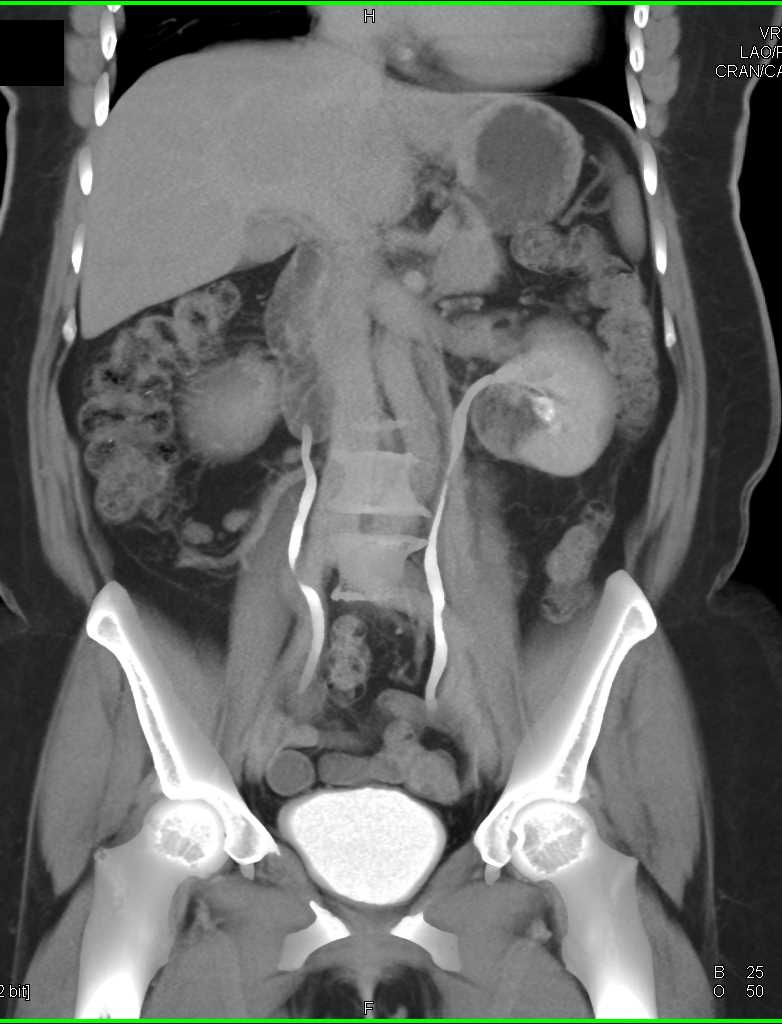

Left Renal Myelolipoma